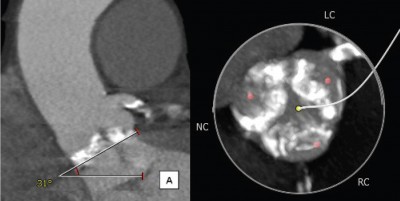

Figura 1. Aspectul vavei aortice la CT multi-slice unde se constată calcificările cuspelor aortice și deschiderea limitată a acestora în incidenţă longitudinală (figura 1a) și transversală (figura 1b).